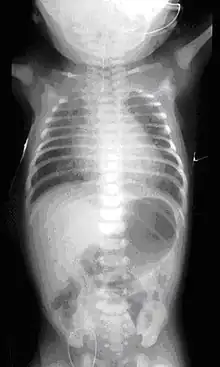

On plain X-ray, a feeding tube will not be seen pass through the esophagus and remain coiled in the upper oesophageal pouch.[8]

If any of the above signs/symptoms are noticed, a catheter is gently passed into the esophagus to check for resistance. If resistance is noted, other studies will be done to confirm the diagnosis. A catheter can be inserted and will show up as white on a regular x-ray film to demonstrate the blind pouch ending. Sometimes a small amount of barium (chalk-like liquid) is placed through the mouth to diagnose the problems.